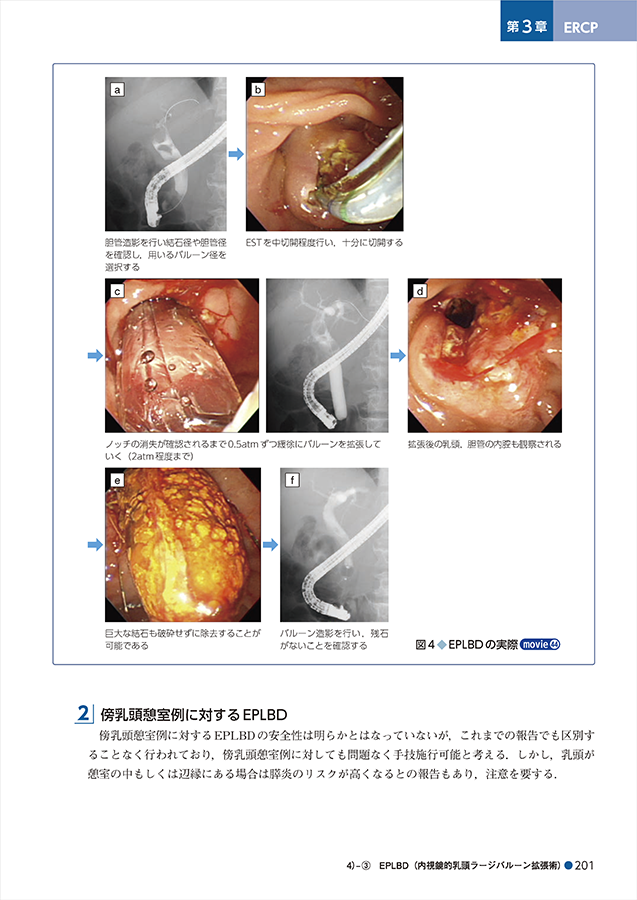

胆膵内視鏡の診断・治療の基本手技 第3版 | 糸井 隆夫 |本。胆膵内視鏡 診断・治療の基本手技 第4版 | 糸井 隆夫 |本 | 通販。胆膵内視鏡の診断・治療の基本手技 第3版 | 糸井 隆夫 |本。国産米粉のホットケーキミックス☆驚くほどもっちり☆MOLINAGA☆2袋セット。胆膵内視鏡 診断・治療の基本手技 第4版 - 羊土社。最先端治療 胆道がん・膵臓がん – 法研。裁断済(バラバラ)の本です。胆膵内視鏡の診断・治療の基本手技 第3版 - 羊土社。。胆膵内視鏡 診断・治療の基本手技 第4版 - 羊土社。胆膵内視鏡でサポートバンドを導入 - 事例紹介|Medicle。内視鏡センター|社会医療法人三栄会 ツカザキ病院。胆膵内視鏡の診断・治療の基本手技 改訂2版」付録DVD。胆膵内視鏡の診断・治療の基本手技 - 羊土社。裁断済みの為、状態が悪いとしていますが、書き込み等ございません。使い方の分かる方のご購入をお願いいたします。JDDWで売上1位を獲得した話題の新刊『これで完璧!胆膵内視鏡の